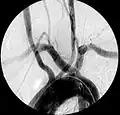

Artère sous-clavière aberrante au scanner axial. (1) trachée, (2) œsophage, (3) Artère sous-clavière aberrante.- Artère sous-clavière droite aberrante à l'angiographie.